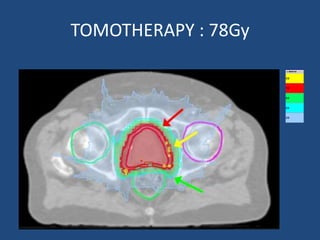

Prostate cancer is the second most common cancer globally, with varying incidence rates influenced by geography and lifestyle changes. In India, prostate cancer cases are rising due to urban migration and increased medical awareness, with current rates approaching those in Western countries. Treatment options vary by stage, including watchful waiting, surgery, radiation therapy, and hormonal treatment, each tailored to patient-specific factors.